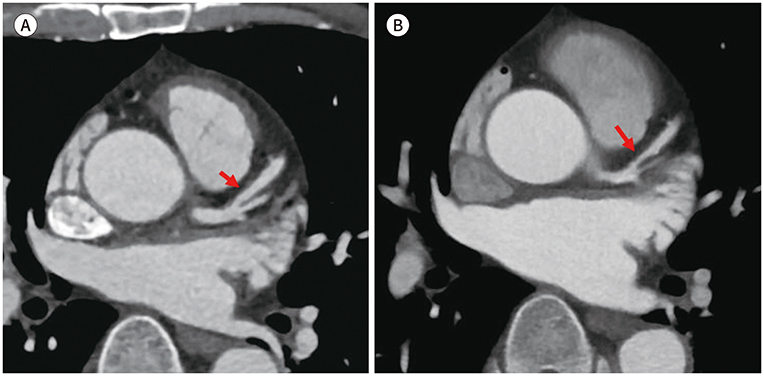

- CT 스캔: 관상동맥 석회화의 상태를 명확하게 볼 수 있는 비침습적인 검사 방법으로, 좌우 심장관의 석회화 수준을 확인할 수 있습니다. 많은 경우, 이 검사는 영화 한 편 보는 시간 안에 가능하여 매우 효율적입니다.